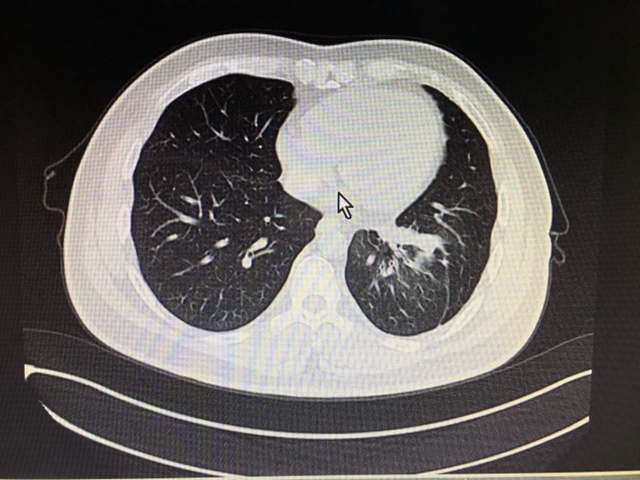

该患者接受治疗前的CT影像: